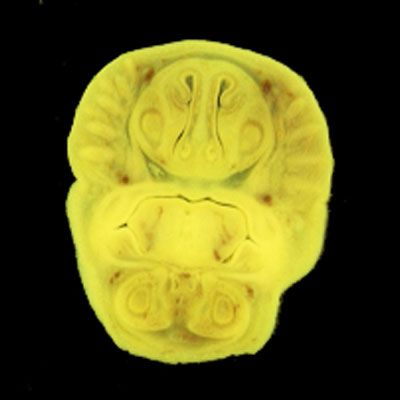

The images below show the normal appearance of Bouin's fluid fixed head sections in specimens at Day 21 of gestation (day mating observed = Day 0).

It is essential that both sides of each section is examined so that structures that exist is several sections can be visualised by the examiner in 3D.

Learning objective: Compare the diagrams with your own specimens and identify all of the structures that have been labelled.

Unlabelled Images